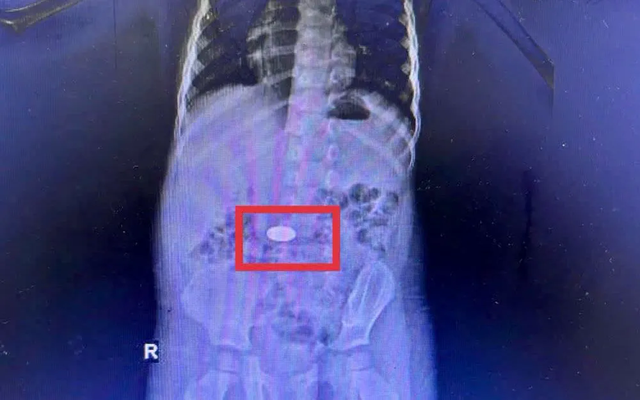

Cảnh báo liên tiếp trẻ nuốt đồng xu nhập viện- Ảnh 1.

Tại Bệnh viện Đa khoa Khánh Hòa, các bác sĩ ghi nhận 5 trẻ nhỏ nhập viện vì hóc đồng xu trong thời gian ngắn. Một trường hợp điển hình là bé 3 tuổi, được đưa đến viện trong tình trạng quấy khóc, khó chịu. Kết quả chụp CT cho thấy dị vật nằm trong dạ dày. Các bác sĩ đã nội soi cấp cứu và lấy thành công đồng xu trong đêm, trẻ ổn định và xuất viện sau đó.